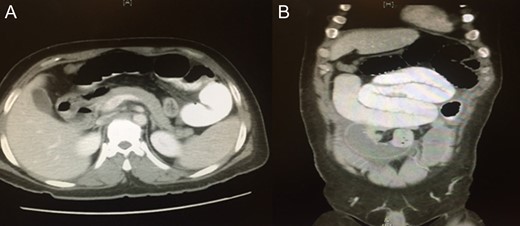

Blood was drawn for a complete blood count, urea and electrolytes, liver function test, coagulation profile, serum glucose level, carcinoembryonic antigen and cancer antigen, and the results were all within normal limits. An initial abdominal X-ray showed multiple air fluid levels and a dilated bowel (Fig. 1A and B). A computed tomography scan of the abdomen and pelvis showed small bowel obstruction to the level of the proximal ileal loops, with a transition point between the dilated proximal loops and the collapsed terminal ileal loops (Fig. 2A and B).

Initial abdominal x-ray showing multiple air–fluid levels (A) and a dilated bowel (B).